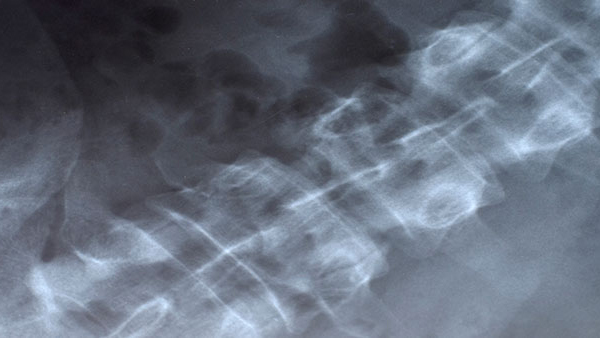

Condition / Treatment Chordoma